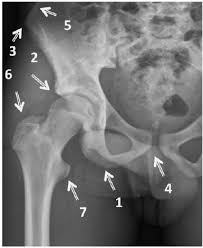

Pelvic Avulsion Fracture Symptoms Causes And Treatment from www.sportsinjuryclinic.net In the pelvis, the newly formed secondary centers of ossification, the apophyses, are the most likely portions of the bone to avulse. In adults, the ligaments and tendons tend to be injured first, whereas in children the bone may fail before. Physical therapy may also help a fracture heal more quickly than immobilization alone. Pelvis injuries range from the benign to life threatening. Your doctor might recommend that you use crutches to keep weight off the hip while it heals. Avulsion fractures are more common in children than in adults. Your doctor might recommend that you use crutches to keep weight off the hip while it heals. Aiis and ischial tuberosity fractures are at increased risk of developing future pain and nonunions, respectively.

Avulsion Fractures Of The Pelvis In Adolescents Eurorad from www.eurorad.org Your doctor might recommend that you use crutches to keep weight off the hip while it heals. An avulsion fracture is an injury to the bone in a location where a tendon or ligament attaches to the bone. When a small piece of the bone breaks off the main bone. Apophyseal avulsion fractures are usually the result of a sudden forceful concentric or eccentric contraction of the muscle attached to the apophysis. In the pelvis, the newly formed secondary centers of ossification, the apophyses, are the most likely portions of the bone to avulse. Your physical therapist will show you how to perform exercises that strengthen the bone and improve your range of motion. They usually happen when a bone is moving one way, and a tendon or ligament is suddenly pulled the opposite way. How good is recovery after pelvic fracture?

Physical exam should not be used to rule out a pelvic fracture in unconscious patients, but it can nearly definitively rule it in. Severe pelvic fractures can be fatal due to internal bleeding or damage to nearby organs, or result in chronic pain and physical disabilities. Exercise increases blood flow, which delivers more. They are not associated with avulsion fractures or stress fractures. Apophyseal avulsion fractures are usually the result of a sudden forceful concentric or eccentric contraction of the muscle attached to the apophysis. Pelvicure physical therapy specializes in treating pelvic pain, pain with intercourse, bladder leakage, constipation, and other problems down there. Like other pediatric fractures, apophyseal avulsion fractures fail through the physis.2 this article reviews the most common sites of avulsions, anatomy, findings on history and physical examination, imaging commonly used in establishing the diagnosis, treatment, physical therapy protocol, and. Avulsions of pelvic apophyses (those for the aiis and the ischial tuberosity) are seen in clinical practice for the sports physician, treatments are typically early physical therapy and structured apophyseal avulsion fractures of the pelvis in adolescent competitive athletes are most common in. Most often, this occurs during sudden movements and changes in direction. In the pelvis, the newly formed secondary centers of ossification, the apophyses, are the most likely portions of the bone to avulse. Aiis and ischial tuberosity fractures are at increased risk of developing future pain and nonunions, respectively. Pelvic fracture is a disruption of the bony structures of the pelvis, including pelvic ring fractures, acetabular fractures, and avulsion fractures. Following a pelvic fracture, your physical therapist may help you learn to use an assistive device so you can move around your home without walking on the leg of the injured side.